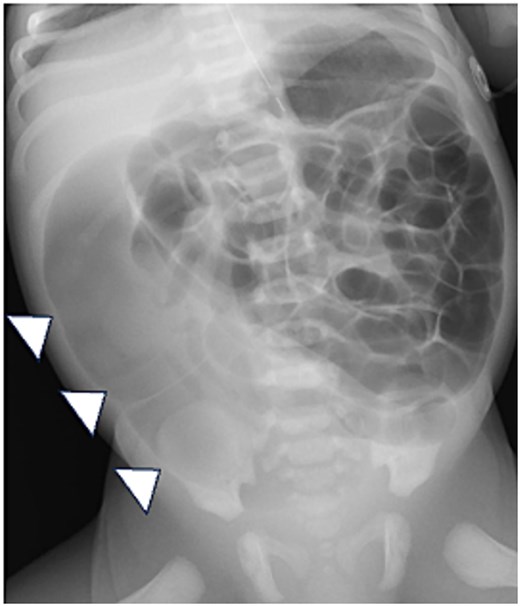

Abdominal ultrasonography. Abdominal ultrasonography showing that the catheter is positioned within the rectum (arrowheads).